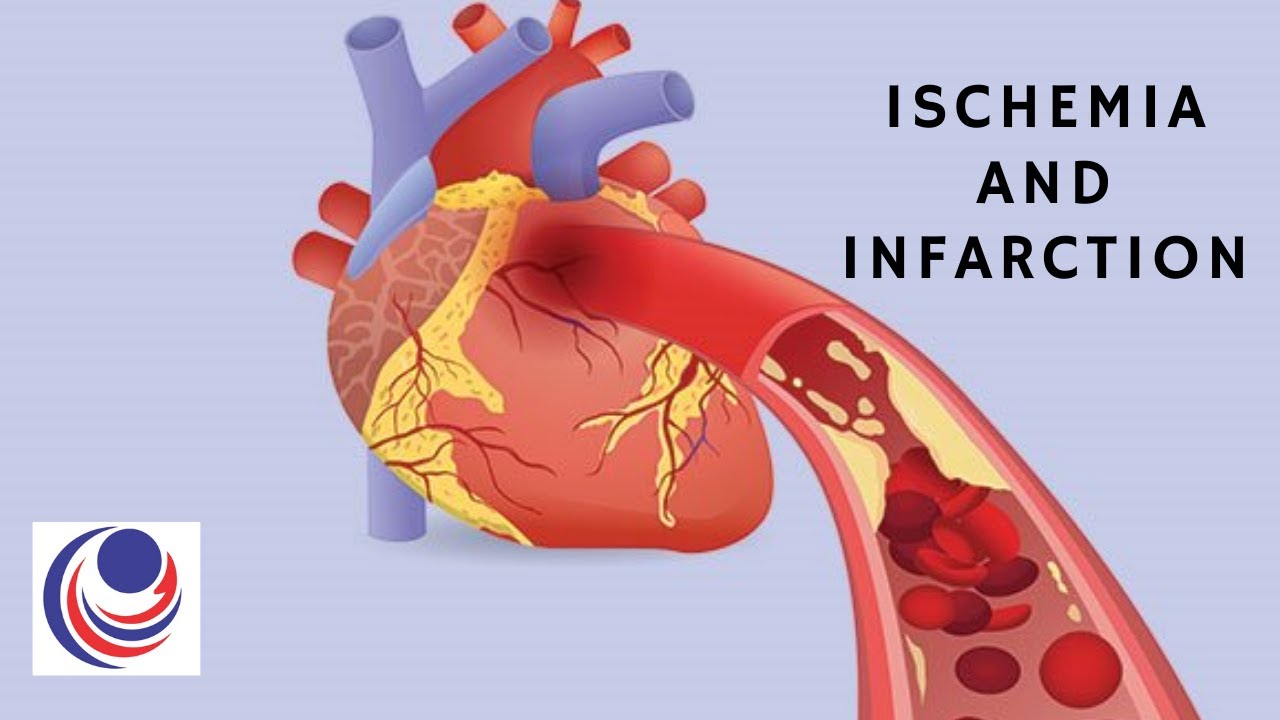

Ischemia and infarction are related but distinct medical conditions Ischemia refers to the reduced blood flow to an organ or tissue which can lead to various symptoms Ischemia is defined as a decrease in blood flow below the level necessary to sustain normal cell structure and function Ischemia can be global as in cardiac arrest or severe oligemia as may

Ischemia can cause a heart attack heart failure and irregular heartbeat It can cause severe pain in the chest called angina pectoris or sudden cardiac death This type of condition when it There are several causes for ischemia a few of them are as follows Cardiac This can result in irregular heartbeats cardiac failure and heart attacks Additionally it may result